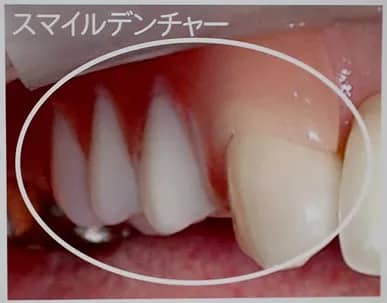

スマイルデンチャー

今までの入れ歯は、銀色のバネを歯にかけて固定していましたが、バネの代わりにピンクのプラスチックで固定するので歯ぐきと見分けづらくなりました。

保険外の診療となりますので、費用についてはご相談ください。